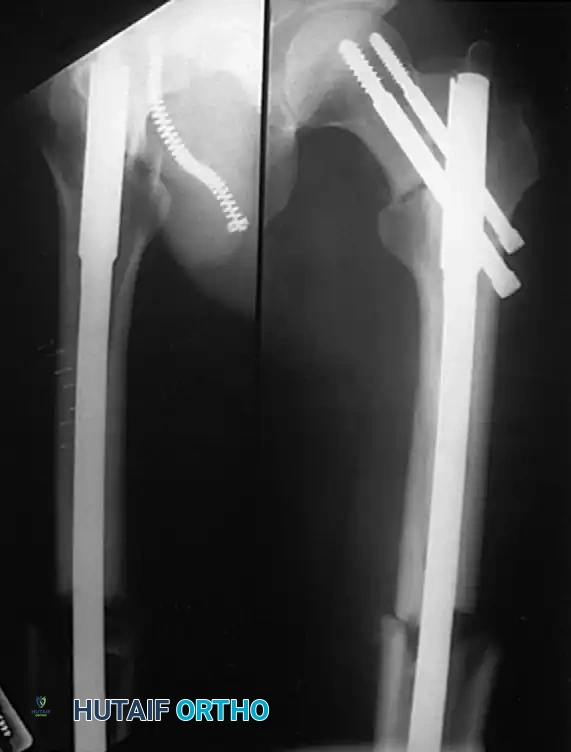

Intramedullary Nailing (The Gold Standard)

Internal fixation of femoral shaft fractures revolutionized trauma care following World War II with the introduction of the Küntscher nail. Today, interlocking intramedullary (IM) nailing is universally considered the treatment of choice for the vast majority of femoral shaft fractures.

In a young adult patient with a fracture through the isthmus of the medullary canal, a reamed, locked IM nail provides the ultimate biomechanical construct. It acts as a load-sharing device, allowing for early weight-bearing, a short hospital stay, rapid return of joint motion, and a high rate of union.

Distal and Proximal Locking

Locking the nail prevents shortening and rotational malalignment, which is especially critical in comminuted (AO Type B and C) fractures.